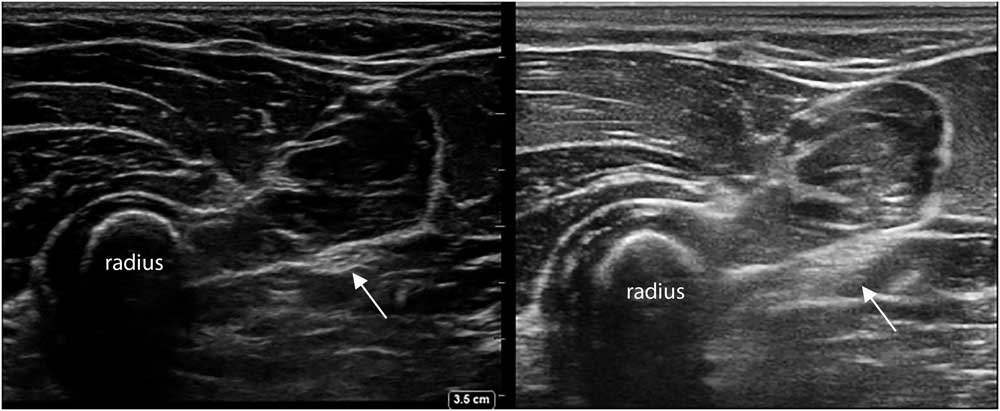

Many factors influence how a muscle or nerve will look on the screen. Every ultrasound machine has a specific set of image-forming properties that determine how the software handles the incoming sound waves from the transducer elements. These system settings, such as the overall gain (i.e., the volume knob), image depth, focal zones, image compression, the use of harmonic waves and spatial or time-averaging techniques create a specific “look” (Figure 3), and most users will become familiar over time with their standard preset images of muscle or nerve. If image clarity and resolution are paramount, as in nerve ultrasound, one wants a machine that can utilize all image optimization tools to provide the best picture. However, if obtaining reproducible and quantifiable images of muscle echogenicity is the goal, a machine with precisely defined preset and no image-enhancing features is ideal (Figure 4).

Figure 3 Two transverses images of the proximal ventroradial forearm, showing the bony structure of the radius with different muscles layered on top, and the median nerve between the fascia (arrow). Notice the difference in overall image appearance; the left image was captured with a Sonosite Xporte system with a 5-16 MHz linear probe and a MSK nerve preset (Fujifilm Sonosite Inc., Bothell, Washington, DC), and the right image was captured with an Esaote MyLab Alpha system with a 3-13 MHz linear probe and an MSK preset (Esaote SpA, Genoa, Italy).